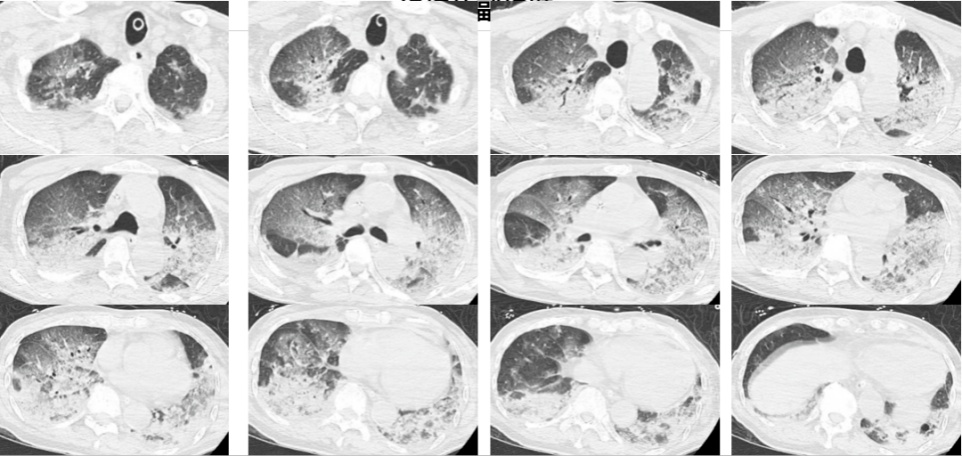

入院时,韩爷爷意识不清,血压、心率下降,医生随即为他安排头颅、胸部CT和肺血管CTA检查,结果显示,老人的双肺出现大面积白色影像。经会诊,韩爷爷被确诊为热射病诱发的肺水肿。